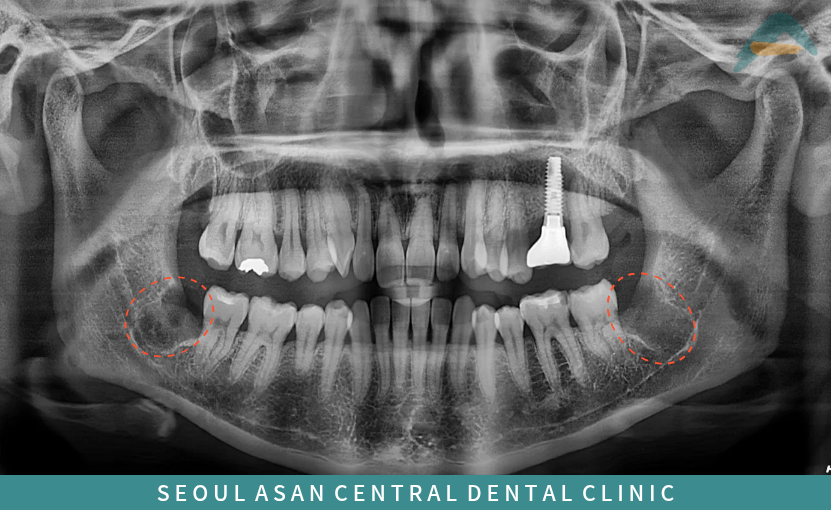

사랑니는 올라오는 시기나 형태가

사람마다 다 다를 수 있으며

턱뼈의 공간 부족으로 인해

비정상적인 방향으로

맹출 하는 경우가 많아

다양한 문제를 유발할 수 있어

사랑니 발치를 진행하기도 합니다.

이렇게 사랑니가 매복되어 있는 상태라면

주변 치아와 신경, 턱뼈 구조물에

영향을 줄 수 있기에

발치 난도가 더 높아지고

더욱 까다로운 요구가 필요한데요.

더불어 치아 뿌리 끝이

신경과 가깝게 위치해 있다면

대학병원으로 의뢰를 하는 경우가 많지만

은행동치과 서울아산센트럴에서는

대학병원급 협진 시스템이 가능함은 물론

오랜 시술 경험을 가진

구강악안면외과 전문의가

상주해 있기 때문에

안정적인 발치가 가능합니다.

사랑니 발치 전에는

3D 정밀진단 장비를 통해

사랑니의 위치와 하치조 신경과의 거리,

눈에 보이지 않는 해부학적 구조물까지

정밀하게 파악한 후 발치를 진행해야 합니다.